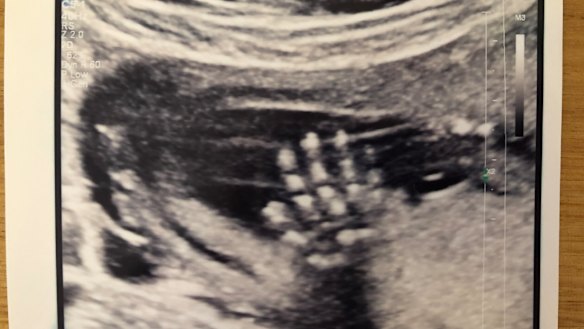

An ultrasound photo of Elizabeth Callinan's daughter Greta "waving".

Instead of being set on a treadmill of anxiety, when we first set eyes on Greta at the 12-week ultrasound my partner and I were able to marvel at her beating heart. We walked out with a black-and-white photo of her little hand fully outstretched, waving at us. I had imagined she was telling me: "I’m here and everything is going to be just fine." I had no idea how important this message would be a few years on.